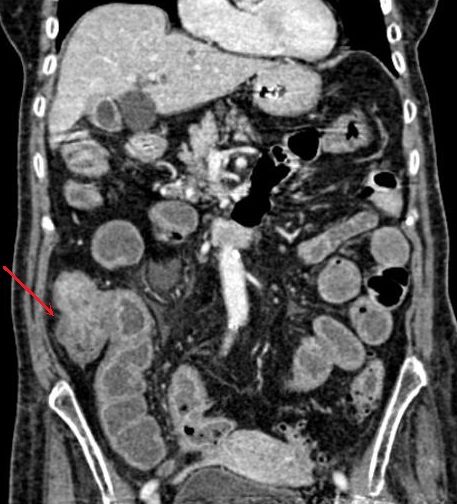

Adenocarcinome du caecum :

Mass hyper-dense en bourgeonante non

homogene du caecum ( fleche rouge ) . Image

radiologique TDM en coupe coronale . |